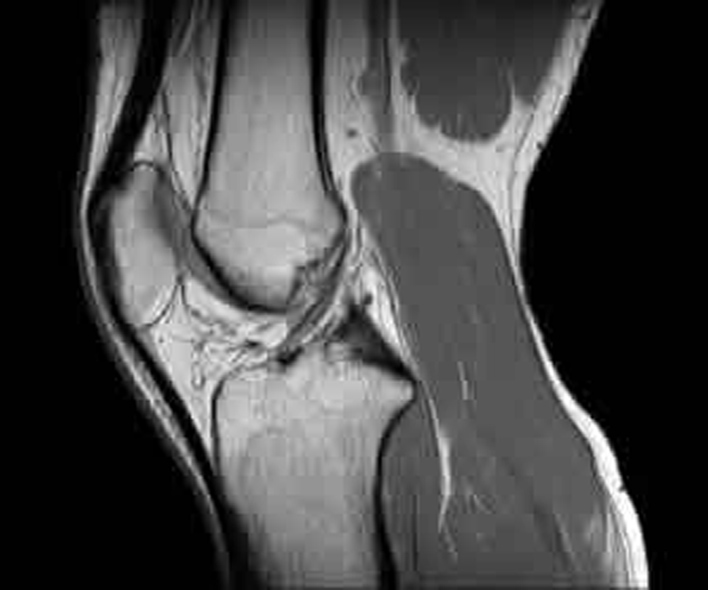

MRIで撮った画像とMRIで分かる疾患の例

膝関節

- 変形性膝関節症

- 膝関節骨壊死症

- 膝関節骨挫傷 などの症状